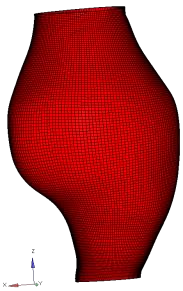

Abdominal Aortic Aneurysm (AAA) is an enlargement in the lower part of the main artery Aorta by 1.5 times its normal diameter. AAA can cause death if rupture occurs. Elective surgeries are recommended to prevent rupture based on geometrical measurements of AAA diameter and diameter growth rate. Reliability of these geometric parameters to predict the AAA rupture risk has been questioned, and biomechanical assessment has been proposed to distinguish between patients with high and low risk of rupture. Stress in aneurysm wall is the main variable of interest in such assessment. Most studies use finite element method to compute AAA stress. This requires discretising patient-specific geometry (aneurysm wall and intraluminal thrombus ILT) into finite elements/meshes. Tetrahedral elements are most commonly used as they can be generated in seemingly automated and effortless way. In practice, however, due to complex aneurysm geometry, the process tends to require time consuming mesh optimisation to ensure sufficiently high quality of tetrahedral elements. Furthermore, ensuring solution convergence requires large number of tetrahedral elements, which leads to long computation times. In this study, we focus on generation of hexahedral meshes as they are known to provide converged solution for smaller number of elements than tetrahedral meshes. Generation of hexahedral meshes for continua with complex/irregular geometry, such as aneurysms, requires analyst interaction. We propose a procedure for generating high quality patient-specific hexahedral discretisation of aneurysm wall using the algorithms available in commercial software package for mesh generation. For aneurysm cases, we demonstrate that the procedure facilitates patient-specific mesh generation within timeframe consistent with clinical workflow constraints while requiring only limited input from the analyst.